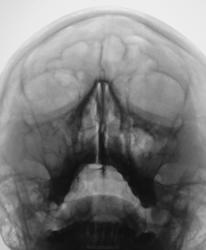

Пол пациента: Женский пол Тип патологии: Другое Область исследования: Челюстно-лицевая область и шея Методы исследования: Rg Жалобы на головные боли. Пациент направлен на рентгенографию ППН. Ваше мнение уважаемые коллеги? https://radiomed.ru/sites/default/files/styles/case_slider_image/public/user/12/2.p1110012a.jpg?itok=qk6hL7ag https://radiomed.ru/sites/default/files/styles/case_slider_image/public/user/12/3.p1110013.jpg?itok=W-Z2Z-n8 https://radiomed.ru/sites/default/files/styles/case_slider_image/public/user/12/4.p1110013a.jpg?itok=40M8zVoz ID:18050 Wed, 11/01/2012 - 18:32 #1 crazyn0lik Offline Last seen: 12 years 8 months ago Joined: 15.09.2010 - 21:22 Posts: 12 Гайморит, фронтит Wed, 11/01/2012 - 19:17 #2 Евгений1313 Offline Last seen: 13 years 2 months ago Joined: 15.10.2010 - 19:13 Posts: 808 Похоже на крупную кисту справа и грубое утолщение слизистой слева. Wed, 11/01/2012 - 19:21 #3 Глазков Игорь А... Offline Last seen: 11 months 3 weeks ago Joined: 19.12.2008 - 20:41 Posts: 1597 в лобных пазухах Прийди к Себе Thu, 12/01/2012 - 20:32 #4 Грицько Виталий Offline Last seen: 9 years 2 months ago Joined: 05.01.2010 - 14:06 Posts: 1058 Глазков Игорь Артурович wrote: в лобных пазухах Добрый вечер! Не могли бы Вы пояснить по эксудату. На мой взгляд изменения за счет слизистой. Fri, 13/01/2012 - 00:43 #5 i_vuduborets Offline Last seen: 11 years 6 months ago Joined: 14.04.2010 - 17:59 Posts: 87 полисинусит

Похоже на крупную кисту справа и грубое утолщение слизистой слева.

в лобных пазухах

полисинусит